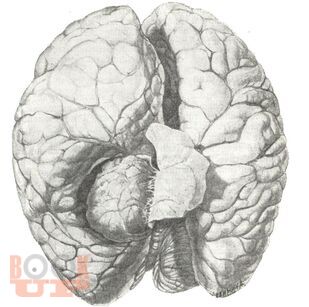

В представленном учебном пособии в виде краткого реферата во введении описано место опухолей головного мозга среди заболеваний у детей, их частота и локализация. Подробно описываются структурно-биологические свойства опухолей головного мозга (астроцитомы, глиобластомы, олигоденд-роглиомы, эпендимомы, менингиомы, краниофарингиомы, сосудистые опухоли, саркомы). Достаточно полно представлены клиника и диагностика опухолей мозга у детей, их особенности в зависимости от пола и возраста ребенка. В кратком заключении описываются затронутые вопросы. Весьма ценными являются вопросы для самоконтроля и тестовые задания. В указателе литературы даны основные источники, в том числе монографии самих авторов.